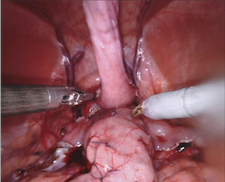

Our challenge was made up of 3 sub-problems. The first was binary instrument segmentation, where each frame was separated into da Vinci Xi instruments and a background class, which contained an ultrasound probe, surgical clips and porcine tissues. The second task was instrument part segmentation, where we scored the participants on whether they could correctly segment each articulating part of the instrument (see Fig. 3). Our final task was to segment and classify the instruments (see Fig. 4).

We provided the first 225 frames of 8 sequences as training data and kept the last 75 frames of those 8 sequences as test data. 2 of the full 300 frame sequences were kept as test sequences. Test labels were kept hidden from the participants. Our datasets contain 7 different robotic surgical instruments. The Large Needle Driver, Prograsp Forceps, Monopolar Curved Scissors, Cadiere Forceps, Bipolar Forceps, Vessel Sealer and additionally a drop-in ultrasound probe, which is typically held in the jaws of the Prograsp Forceps instrument. Samples from the training datasets are depicted in Fig. 2 and examples of the different instrument types are shown in Figure 3 and 4.

IV-C Parts Segmentation

Our second challenge was on instrument part segmentation where the participants were challenged to divide the binary instrument labels into a shaft, wrist and jaws. As in the binary segmentation challenge, the drop-in US probe and other man-made devices as well as all anatomical objects were to be labelled as background. We compute the mean IoU for each frame of each dataset and for frames where no instance of a class occurred, such as when the shaft is withdrawn completely from the field of view. Nine teams participated in this challenge, the only team abstaining was from IIT Delhi.

IV-D Type Segmentation

The final challenge was to identify each instrument type from the list of Large Needle Driver, Prograsp Forceps, Monopolar Curved Scissors, Vessel Sealer, Fenestrated Bipolar Forceps and Grasping Retractor (see Fig. 4). Only 6 teams participated in this challenge, due particularly to the significant increase in difficulty in recognizing many of the da Vinci instruments from one another.